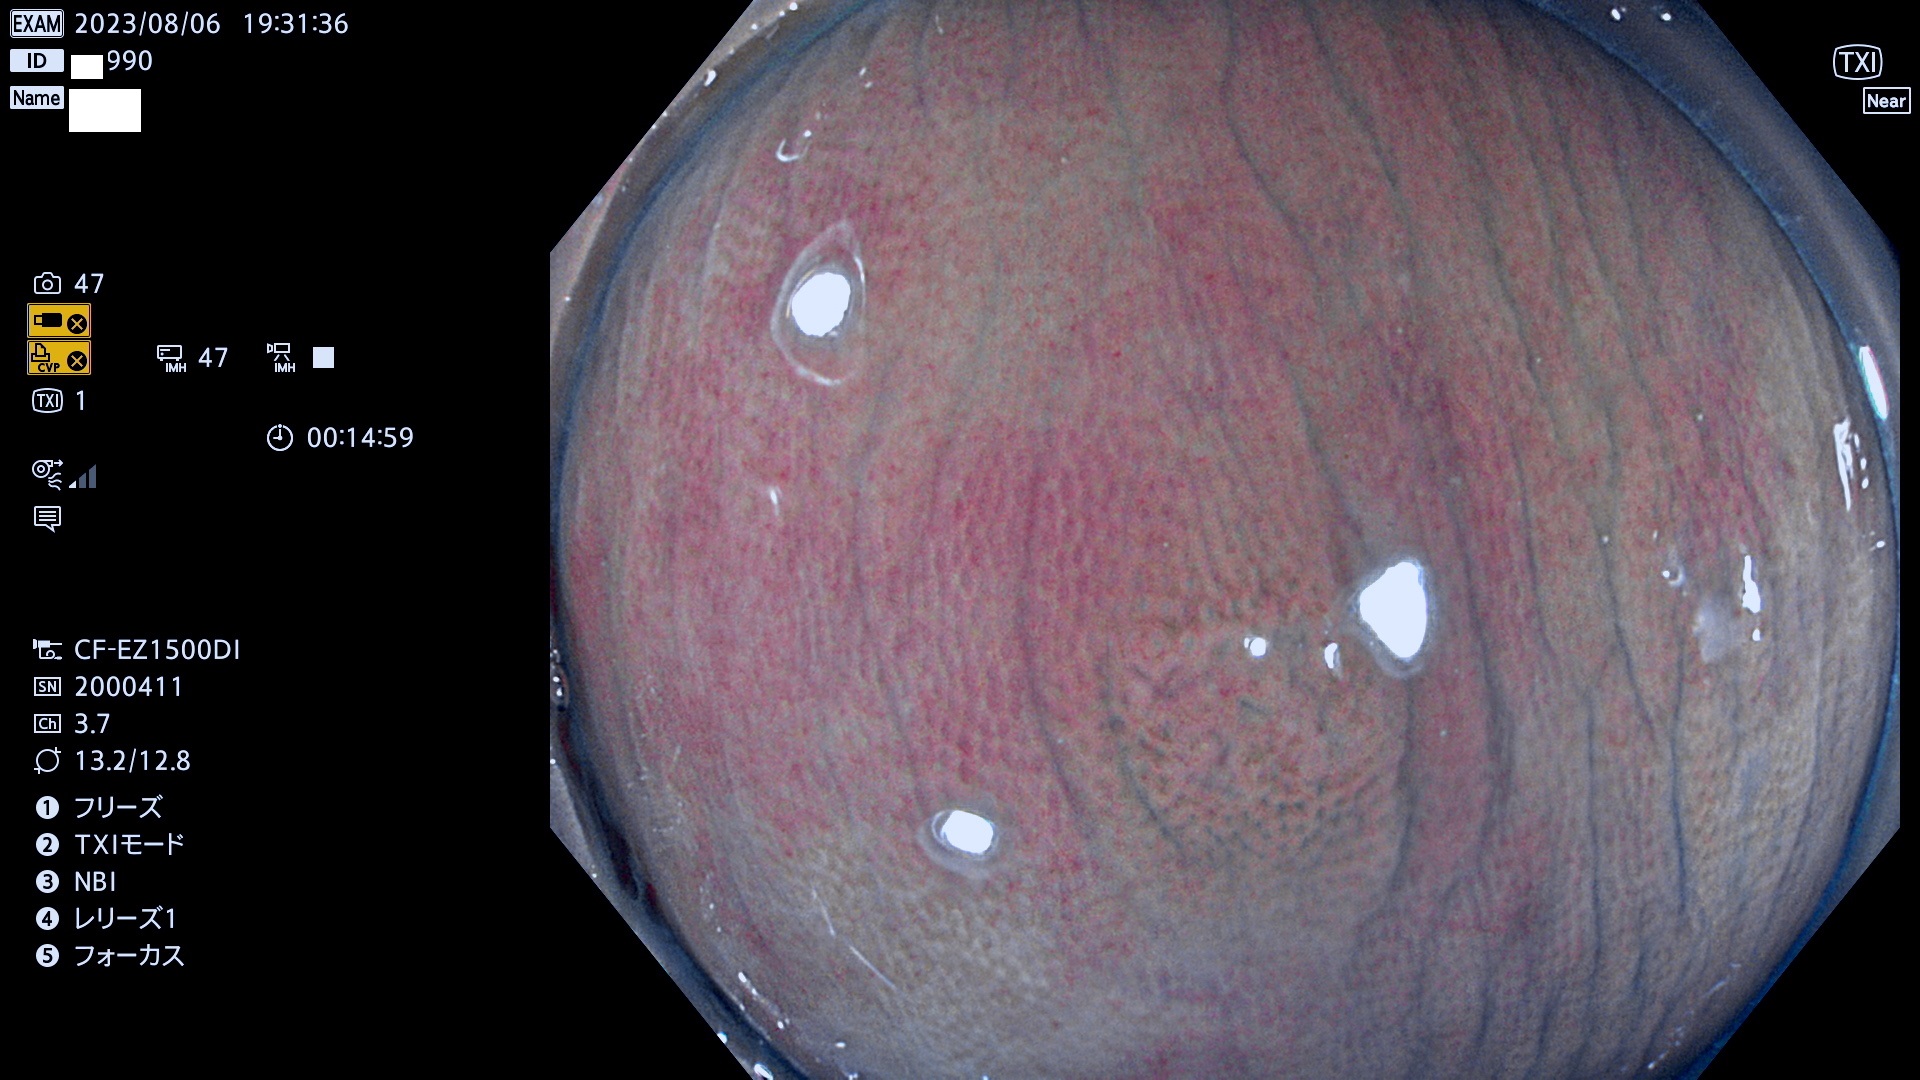

表面型腺腫(Flat Adenoma)の中で、完全に平坦な物をUb、陥凹している物をUcと呼びます。平坦隆起型(Ua)よりも、発見が難しく危険な病変です。このタイプは「内視鏡後・大腸癌の重要犯人」であり、この発見率は「腺腫発見率」よりも、重要な意味があります。

毎週の検査(木・金・土・日)に発見されたUb、Uc型・腺腫を、その週の日曜の夜にUPし1週間、提示します。

抽出の対象期間 2023年8月3日(木)〜8月6(日)の4日間(48件の検査)5件